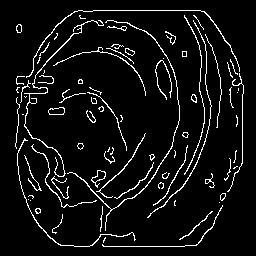

The performance metrics for Edgeconnect and AOTGAN on the validation data after fine-tuning the models, are shown in Table II. In addition to qualitative evaluation, Figure 3 provides example data from the different steps of the PolypConnect pipeline using the EdgeConnect model and the AOTGAN model. Due to obvious visual differences in the generated polyps between the models, we selected the EdgeConnect model as the main polyp inpainting model of the PolypConnect pipeline for further evaluation and qualitative assessment by domain experts.

(a) Refer to caption Refer to caption Refer to caption Refer to caption Refer to caption Refer to caption

(b) Refer to caption Refer to caption Refer to caption Refer to caption Refer to caption Refer to caption

(c) Refer to caption Refer to caption Refer to caption Refer to caption Refer to caption Refer to caption

(d) Refer to caption Refer to caption Refer to caption Refer to caption Refer to caption Refer to caption

(e) Refer to caption Refer to caption Refer to caption Refer to caption Refer to caption Refer to caption

(f) Refer to caption Refer to caption Refer to caption Refer to caption Refer to caption Refer to caption

(g) Refer to caption Refer to caption Refer to caption Refer to caption Refer to caption Refer to caption

(h) Refer to caption Refer to caption Refer to caption Refer to caption Refer to caption Refer to caption

Figure 3: Sample data used and generated in the different steps of PolypConnect pipeline. (a) - real polyp images, (b) - manually annotated polyp masks, (c) - randomly selected colon images used as input to the final step of PolypConnect, (d) - extracted edge images of row c. (e) - extracted edge images of polyp regions of row a using the masks of row b. (f) - combined edge images of row d and f. (g) - generated polyp on the images of row c using EdgeConnect. (h) - generated samples from AOTGAN.